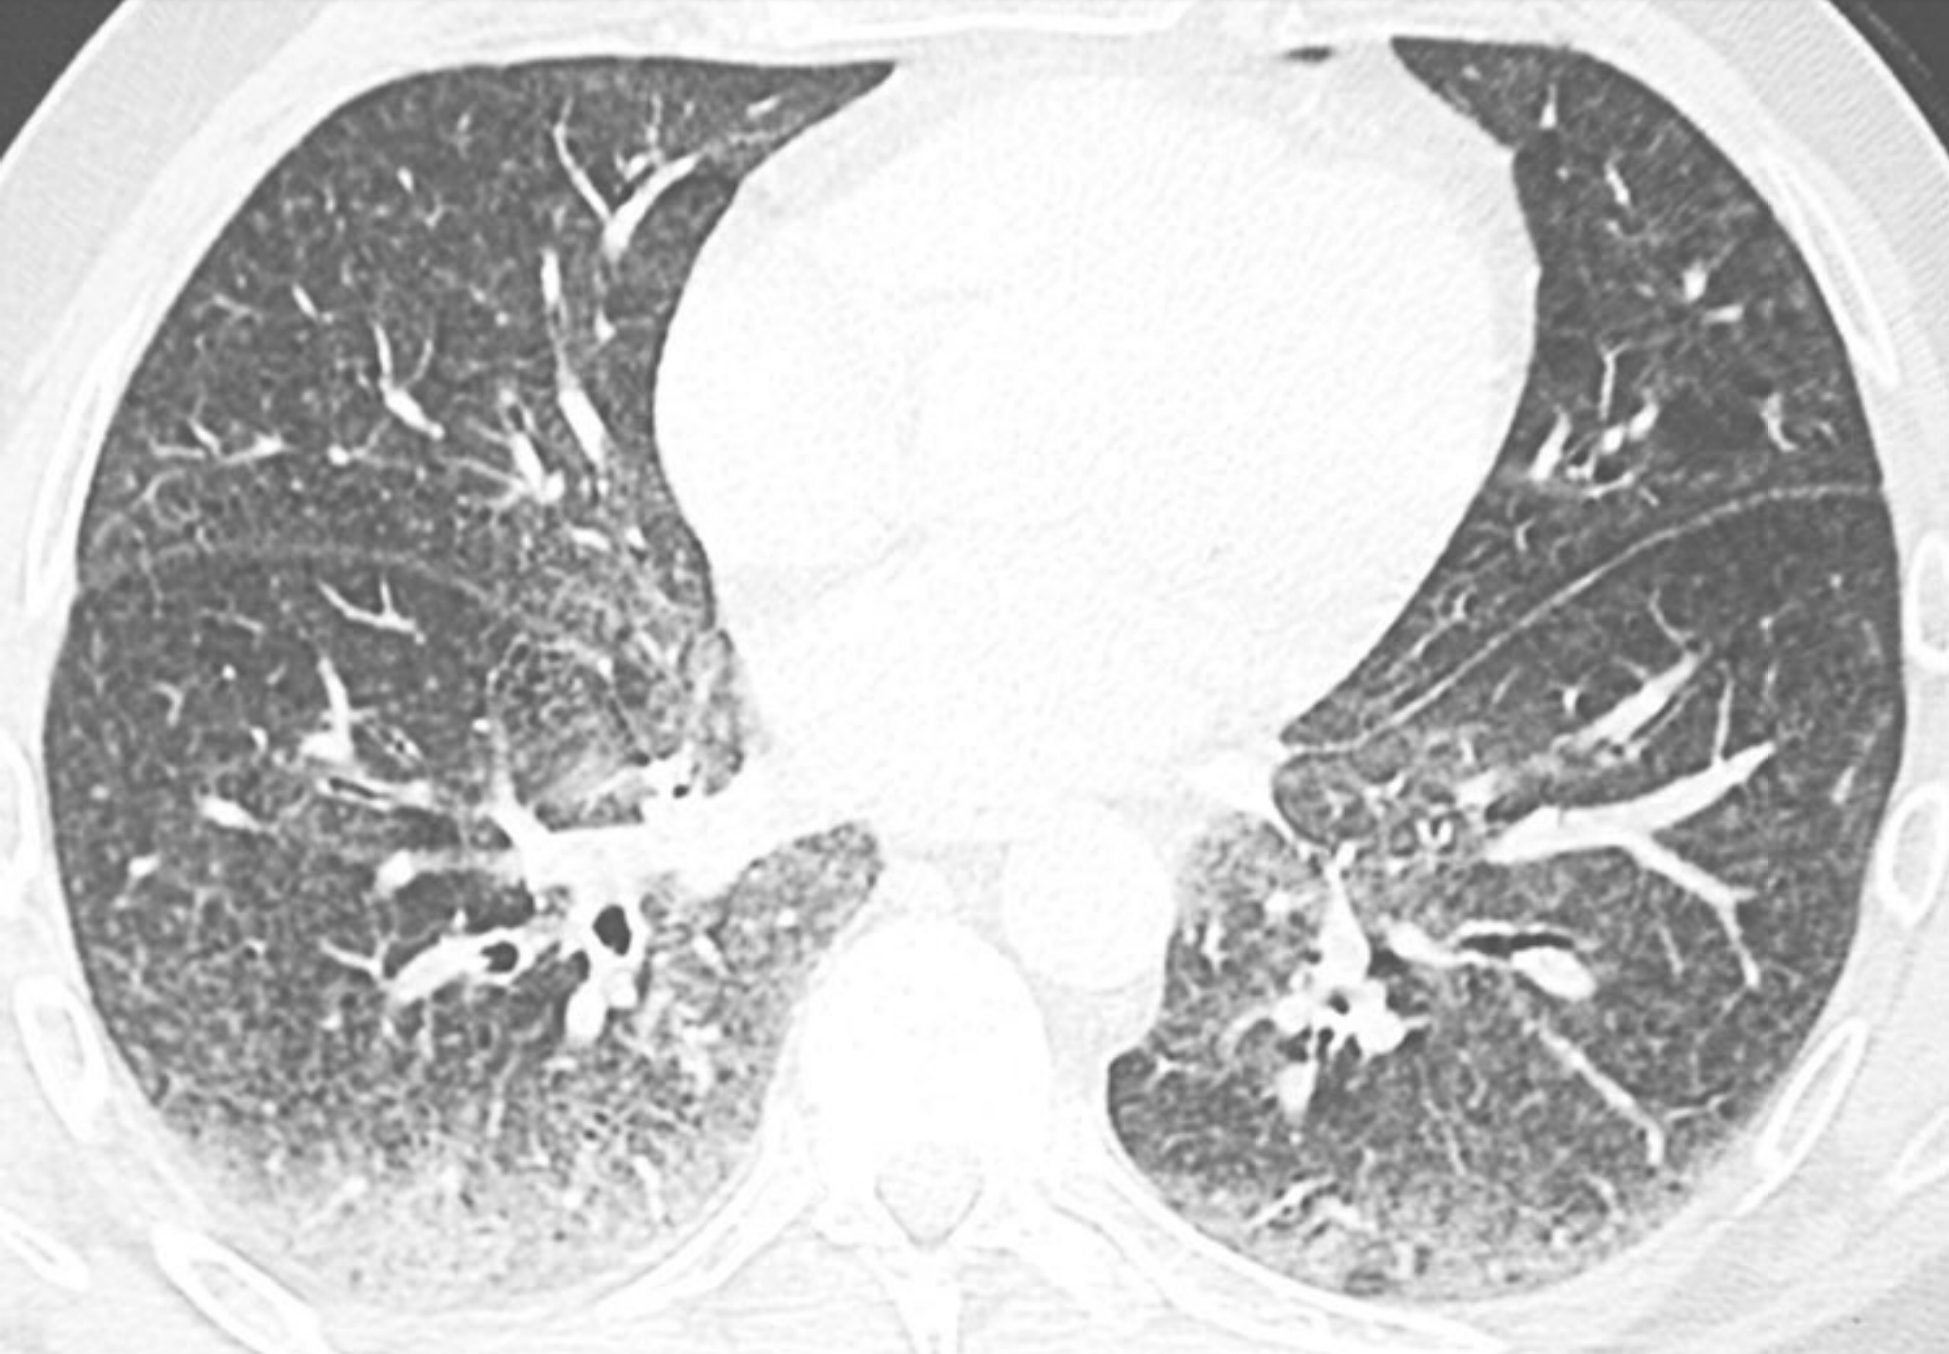

d9aa28845b7cba2a1759d5760b020659.png

异常病变的HRCT分布特征在诊断中的价值。

A.纤维型非特异性间质性肺炎相关的硬皮病患者,HRCT显示以肺外周及胸膜下区分布为主的异常表现;

B.结节病患者,HRCT异常表现主要分布在肺门区及支气管周围,而相对未累及胸膜下区。对于慢性症状的病例,胸膜下及肺基底部分布为主的病变提示普通型间质性肺炎、非特异性间质性肺炎或脱屑性间质性肺炎。弥漫性或者中心轴分布是间质性肺炎的不典型分布,提示其他疾病,如过敏性肺炎或结节病。